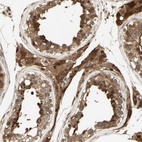

Immunohistochemistry analysis in human testis and liver tissues using Anti-SERPINB6 antibody. Corresponding SERPINB6 RNA-seq data are presented for the same tissues.